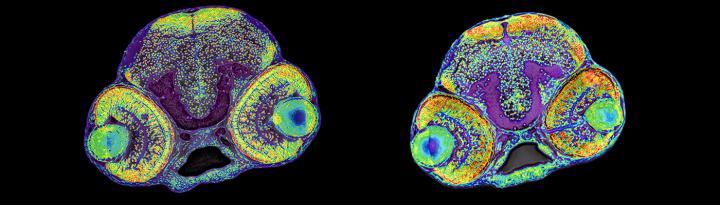

image: The research team used stem cells and zebrafish to investigate the role of RRP7A in brain development. The picture shows the brain of a normal zebrafish larvae (left) and a larvae with microcephaly (right).

The scientists started with genetic analyses of a large family in which children were born with primary microcephaly; a rare congenital brain disorder characterized by a reduction in the size of the cerebral cortex and varying degree of cognitive dysfunction. The scientists found that the children were carriers of a mutation in both copies of the gene, RRP7A, and by the use of stem cell cultures as well as zebrafish as model organism, RRP7A was shown to play a critical role for brain stem cells to proliferate and form new neurons. This process is extremely complex and slight disturbances may have serious consequences, which may explain why the mutation affects the brain and no other tissues and organs.